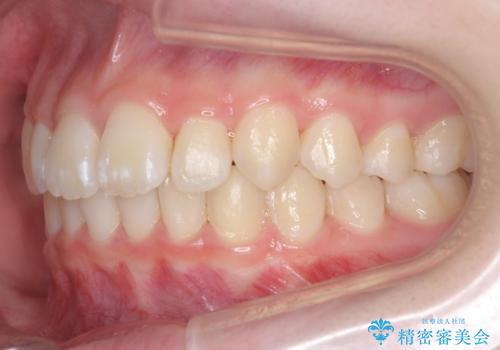

子供の出っ歯 生え代わりと成長期を利用して非抜歯で矯正

- 出っ歯を主訴に来院。

生え代わりを待ってから矯正を始めました。

特に右側のかみ合わせがずれていたため、上の奥歯を後ろに下げています。

下顎も前方に成長し、前歯のかみ合わせも同時に深かったのを浅くすることができました。